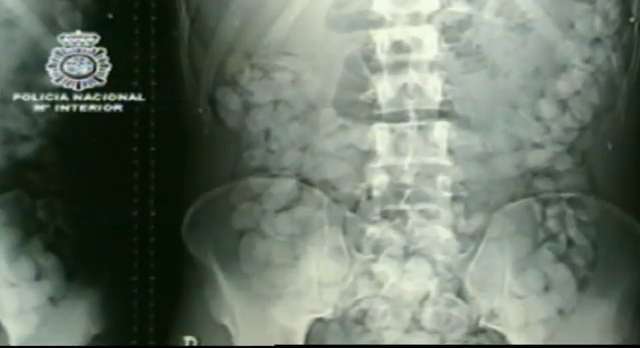

El bebé se encuentra en buen estado en el hospital de Son Llàtzer, de Palma, mientras que la madre ha ingresado en el módulo de detenidos del hospital de Son Espases. En una exploración radiológica posterior se averiguó que, además, la mujer tenía otros objetos extraños en el estómago y en los intestinos, por lo que fue avisada la Policía. Para evitar que el niño resultara dañado, los médicos decidieron extraer el bebé a la embarazada , que después arrojó otras 53 bolas con cocaína que había ingerido.

Según la Policía, la mujer llevaba en su interior cerca de un kilo y cuarenta gramos de cocaína. La presunta traficante fue trasladada este martes al módulo de detenidos de Son Espases, donde la Policía le comunicó su detención por un delito de tráfico de drogas.